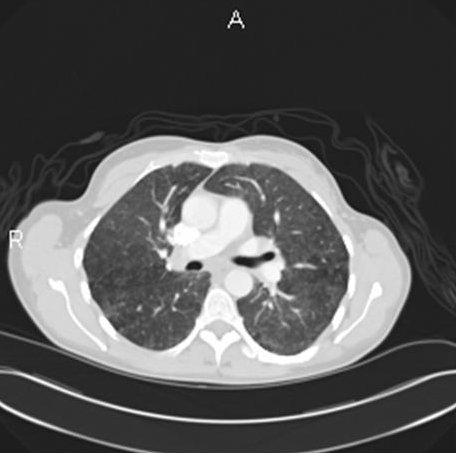

Her chest radiograph showed bilateral interstitial infiltrates without any mediastinal or hilar lymphadenopathy. Her laboratory evaluation revealed a normal complete blood count, chemistry panel, B- type natriuretic peptide level, cardiac isoenzymes, and erythrocyte sedimentation rate. Her antinuclear antibody levels were normal. Her purified protein derivative (PPD) skin test showed less than 5 mm induration at 48 hours. Hypersensitivity pneumonitis screen was negative for the following antigens: Aspergillus fumigatus, Micropolyspora faeni, pigeon serum, thermophilic actinomycetes, and Saccharomonospora viridans. A spiral computerized tomography scan of her chest ruled out pulmonary embolism and revealed bilateral ground glass opacities with diffuse micro-nodular appearance (figure 1).

Figure 1: A spiral computerized tomography scan of her chest on presentation